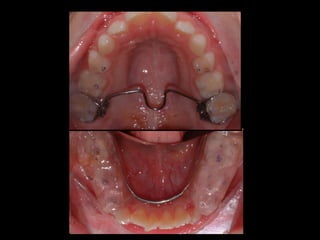

INTRUSIÓN MOLAR BARRA PALATINA BAJA

BARRA PALATINA CORRIGIENDO LA ROTACIÓN MOLAR SE PUEDE GANAR 1-2 MM DE LONGITUD DE ARCADA POR LADO

BARRA PALATINA CORRIGIENDOLA ROTACIÓN MOLAR SE PUEDE GANAR 1-2 MM DE LONGITUD DE ARCADA POR LADO